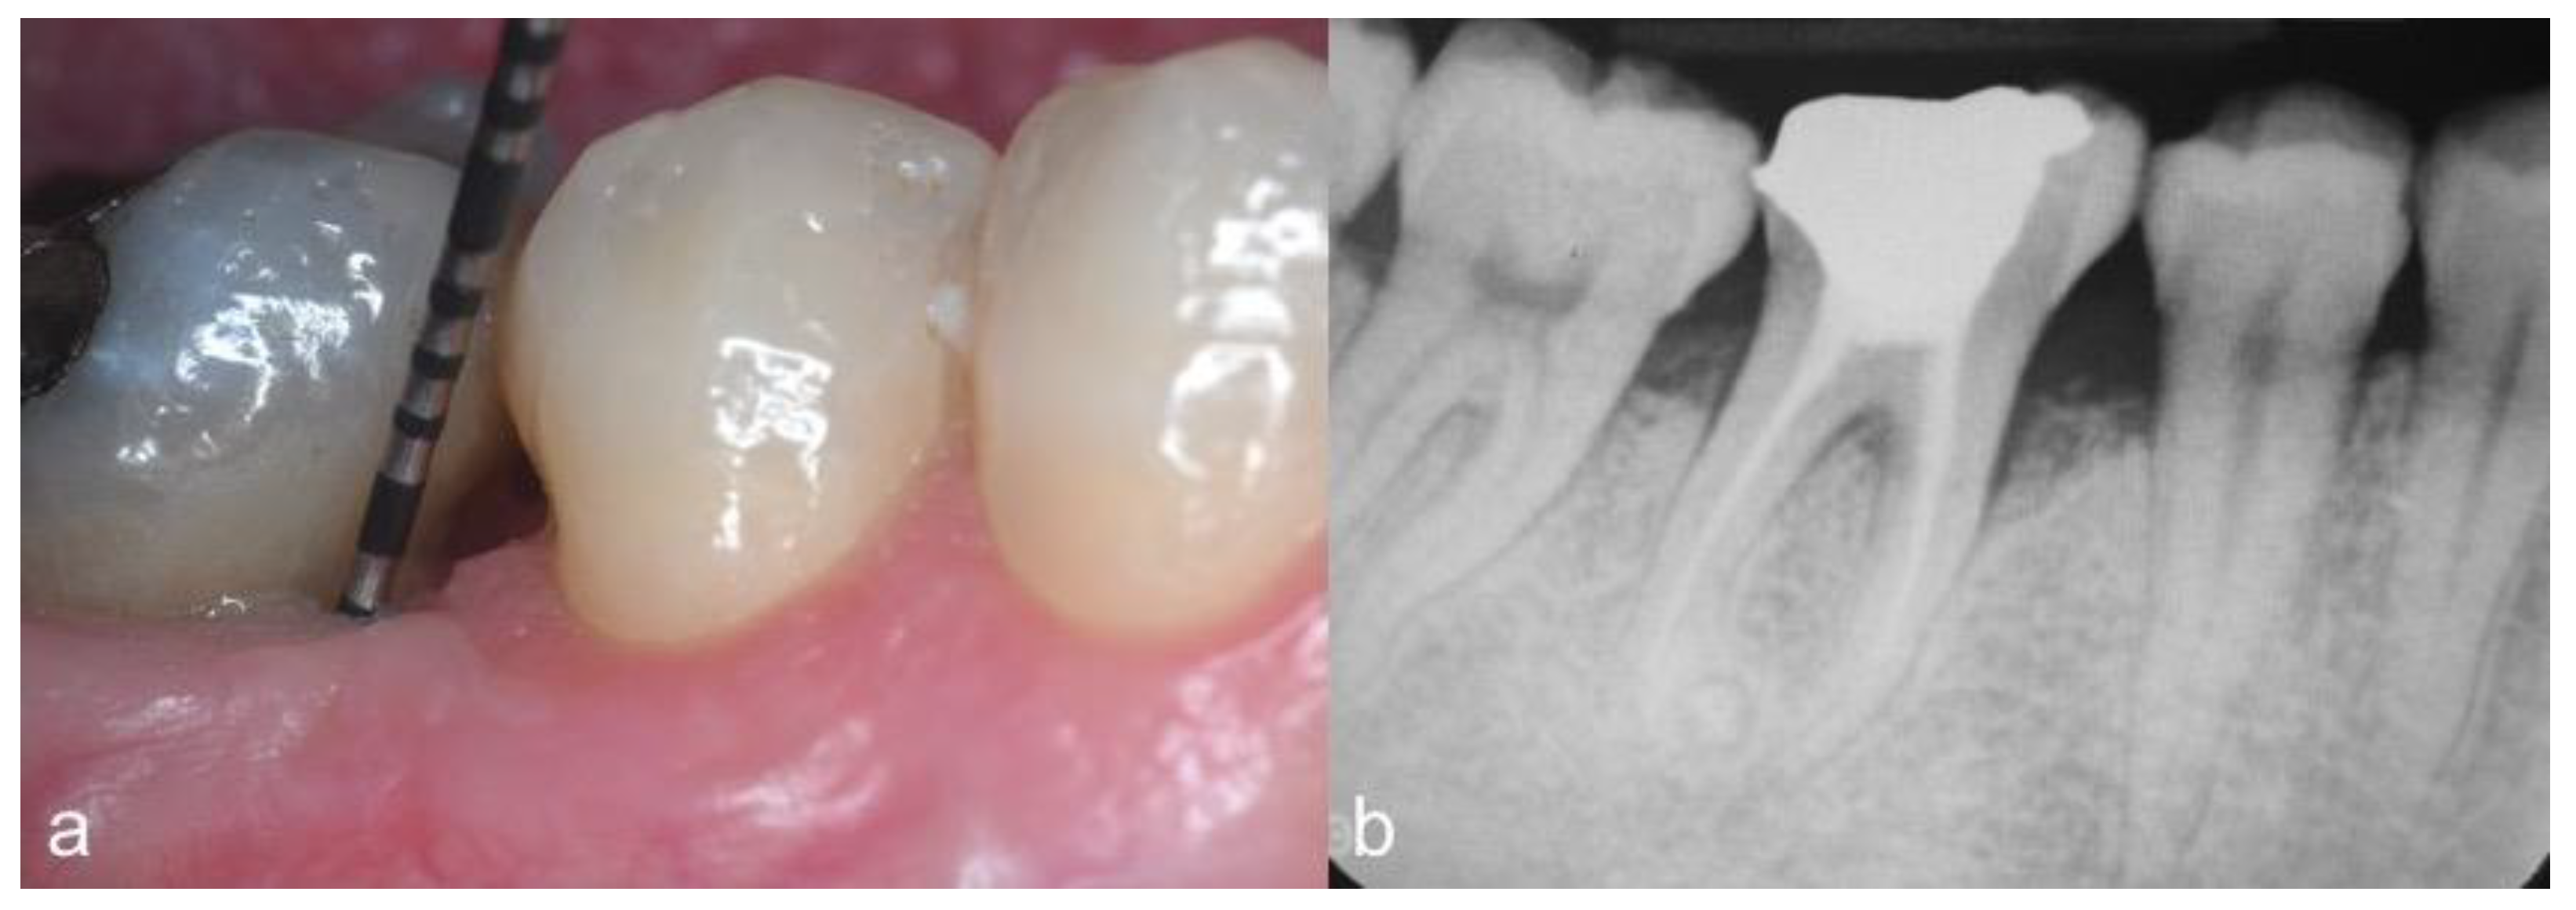

2.4. Follow-Up and Outcomes